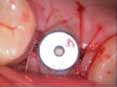

Case 1: Osteotome sinus lift with simultaneous implant placement

A 53-year-old female with a medical history of hypothyroidism, seasonal allergies, and asthma taking Synthroid and Singula presented to my office with pain in No. 3, failed root canal therapy, and a fracture. The tooth was deemed hopeless and extraction and implant placement was treatment planned. Under local anesthesia, tooth No. 3 was sectioned into three pieces and extracted. The sockets were debrided, filled with gel foam, and closed with chromic gut sutures. Healing was uneventful. The patient did not return for two years for follow-up. A CT scan was taken, which confirmed that approximately5 mm of bone remained below the floor of the sinus. After reviewing the options with the patient, a treatment plan of an internal sinus lift (osteotome), bone graft, platelet-rich fibrin (PRF) and simultaneous implant placement was agreed upon. Under local anesthesia, a full thickness flap with two vertical releasing incisions was performed at tooth No. 3 site. A trephine bur was used to a depth of 4 mm. An osteotome was then employed to infracture the bone core, which remained attached to the Schneiderman membrane. A bone graft consisting of DFDBA, anorganic bovine bone, and PRF was used in the osteotomy to increase the vertical bone height using sequential osteotomes. After sufficient elevation, a 7x9 tapered implant was placed on low speed to 50% of the implant depth. The remaining placement of implant was done with a hand torque on 50 ncm to allow for further expansion of the alveolar housing. A healing abutment was placed using the principles of platform switching. Healing was uneventful, and integration was successful.

Case 1: Implant and osteotome bone graft through the socket with Southern Implant